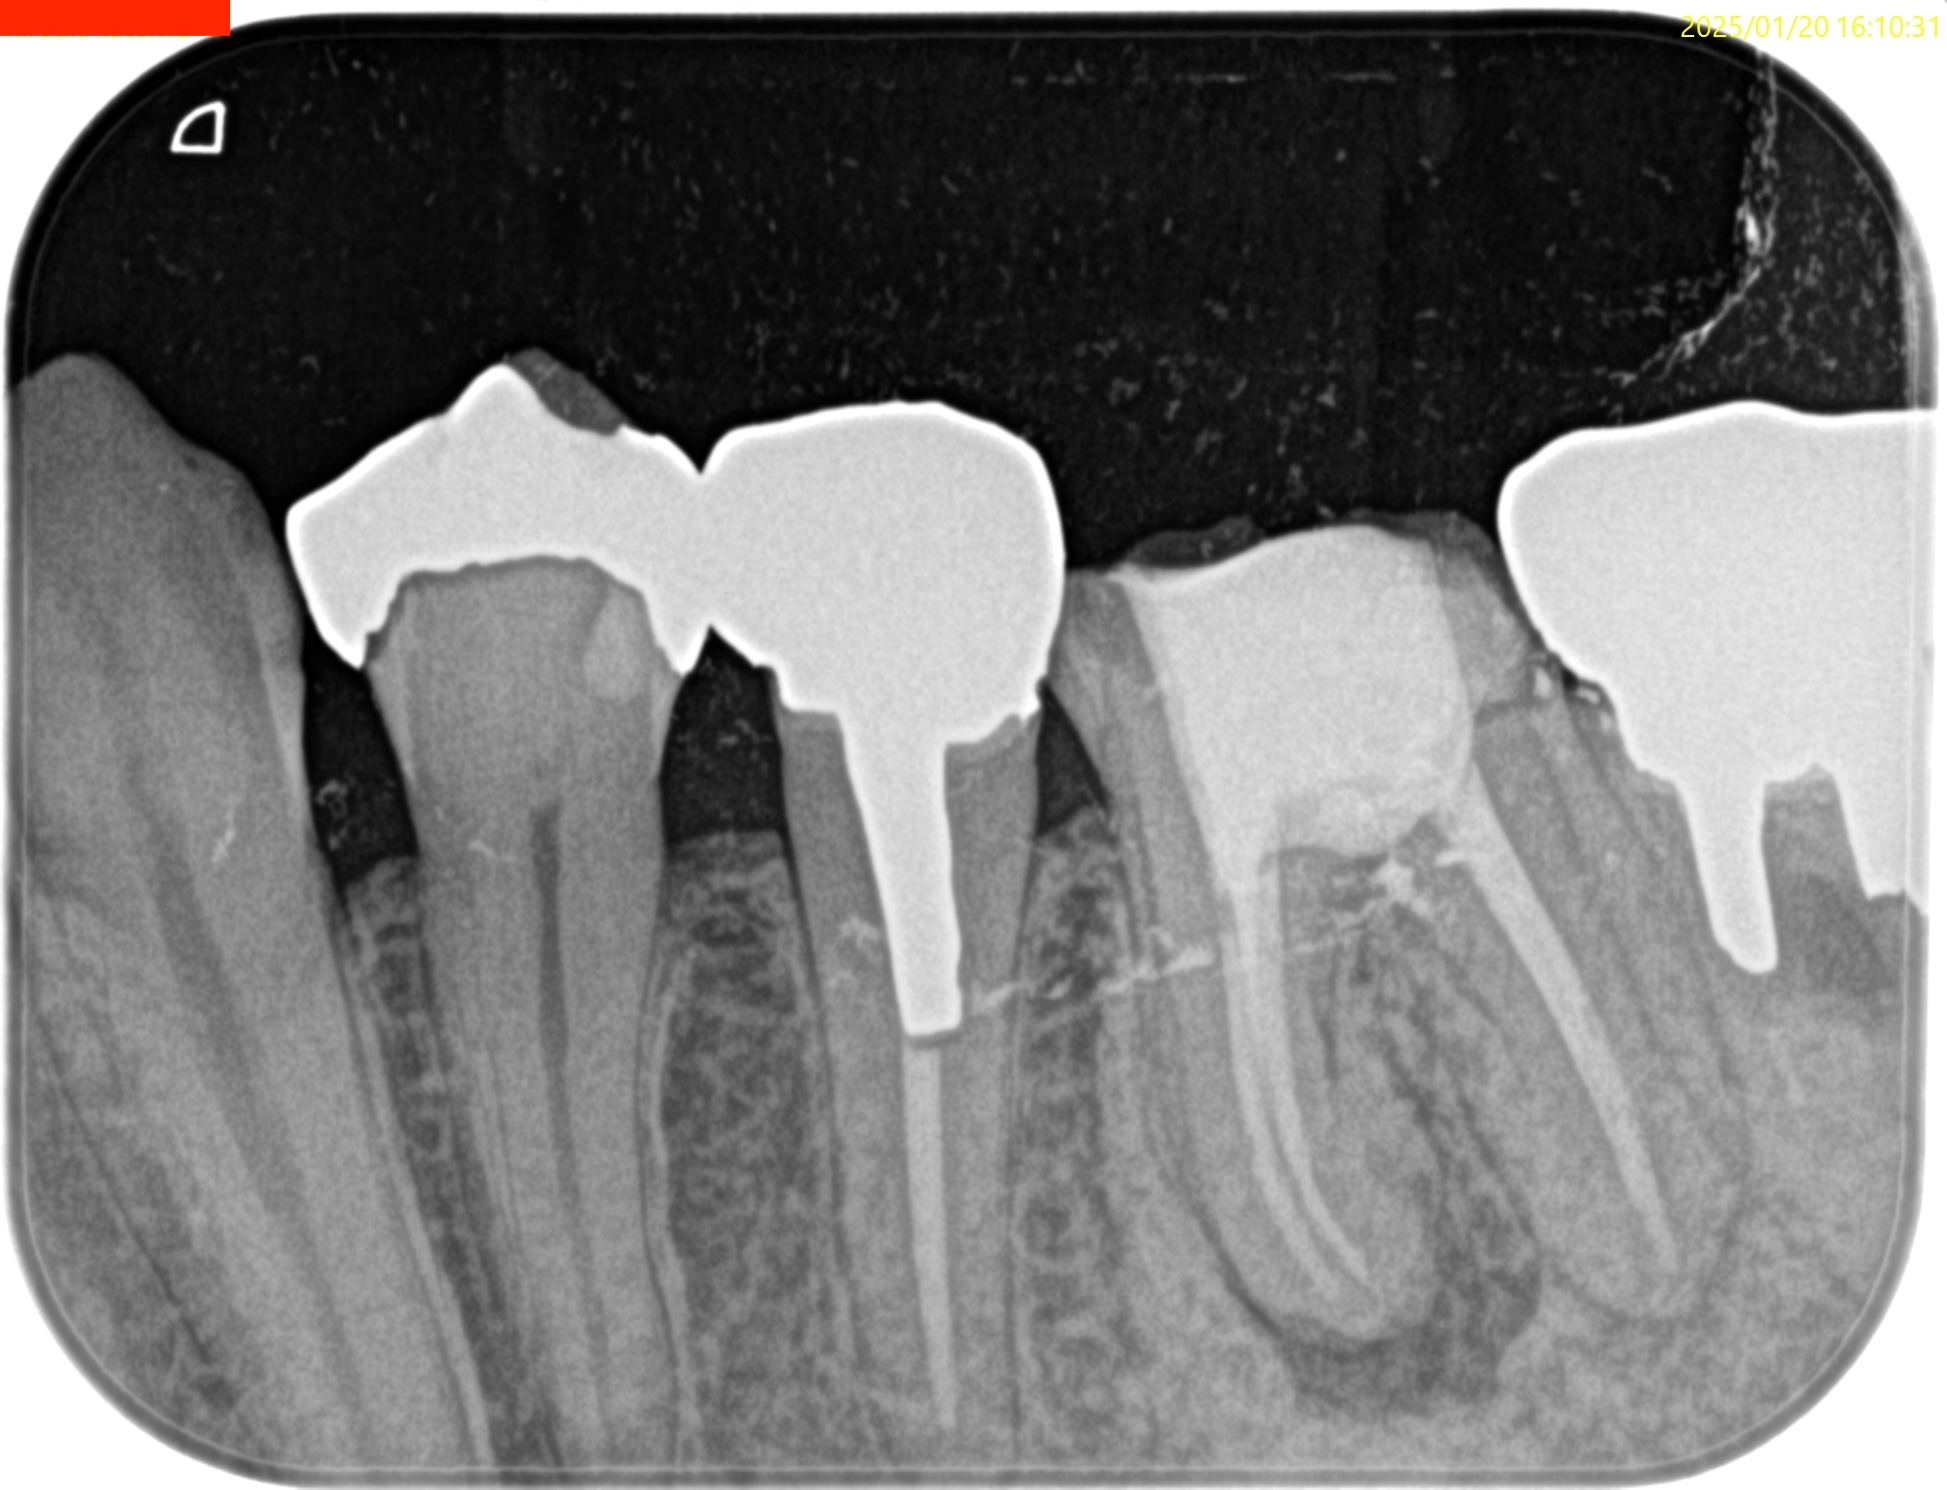

#19 Re-RCT 1yr recall(2026.1.13)

#19

MB

ML

D

術前に大きな根尖病変が存在していたM根のそれは消失はしていないが大幅に縮小し、

術前に根尖病変がなく再根管形成・充填しなかったD根はやはり依然として根尖病変はできていない。

このケースでも

Selective Root Canal Retreatmentが奏功している。

ということで根尖病変は完全消失はしていないのでまた1年後に経過を見せてもらうことになった。